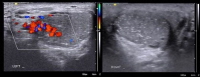

Chẩn đoán hình ảnh với siêu âm Doppler màu xác định có giãn tĩnh mạch thừng tinh phải có 2 tiêu chuẩn chính:

- Có ít nhất một tĩnh mạch có đường kính trên 2mm.

- Có hồi lưu tĩnh mạch khi thực hiện nghiệm pháp Valsalva.

Nghiệm pháp Valsalva dương tính khi cho bệnh nhân hít thật sâu và giữ lại hơi thở hay ho thật mạnh làm tăng áp lực ổ bụng và tăng áp lực tĩnh mạch, sẽ thấy dòng máu trào ngược vào tĩnh mạch và đo được sự thay đổi áp lực này.